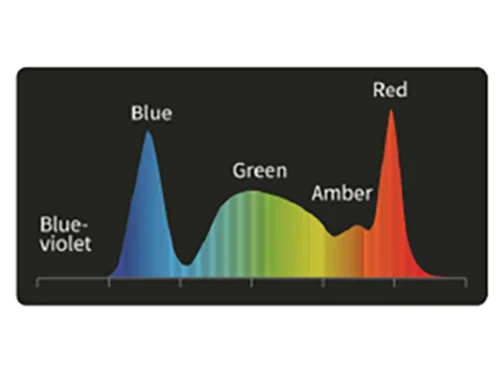

DSI: Узкоспектральная двухцветная визуализацияа

Свет фиолетового и зеленого спектров наиболее эффективно поглощается гемоглобином, что снижает отражение и рассеяние и позволяет четко визуализировать поверхностные сосуды слизистой оболочки. Увеличивает контраст между кровеносными сосудами и окружающей тканью.

PSI: Спектральная визуализация цветовой палитры полихроматическая визуализация

Выравнивает пропорции узкополосного фиолетового и красного цвета на основе белого цвета и использование алгоритмов сложения для повышения цветового контраста.